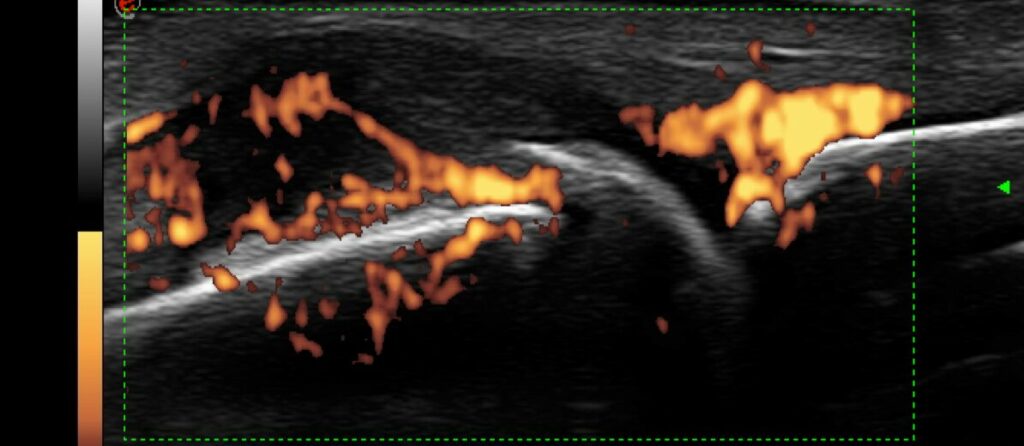

Comparison of power Doppler ultrasound and serum Vascular Endothelial Growth Factor (VEGF) in patients with rheumatoid arthritis under anti-inflammatory treatment.

Parysa Alborz a; Elena Neumann b; Ulf Müller-Ladner b; Johannes Strunk a;

a Krankenhaus Porz am Rhein, Abteilung für Rheumatologie, Urbacher Weg 19, 51149 Köln, Germany

b Kerckhoff Klinik, University of Giessen, Department of Rheumatology and Immunology, Beneckestr 2-8, 61231 Bad Nauheim, Germany